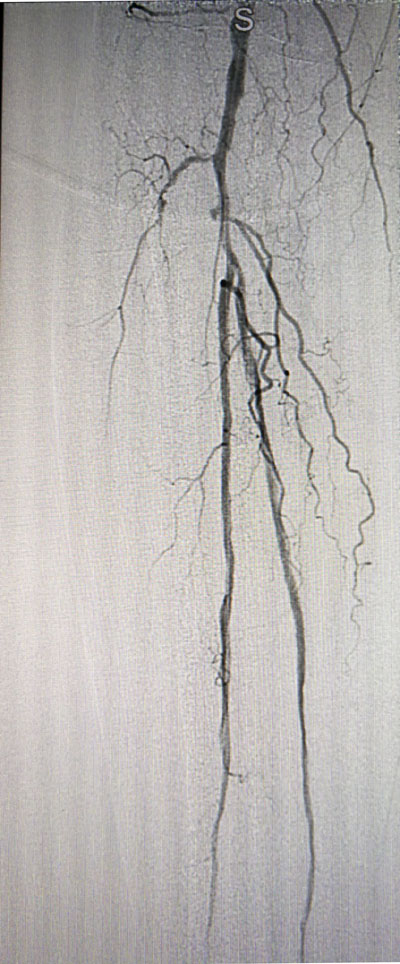

放射科导管室内做好了术前准备,患者由无创呼吸机及各种循环支持下开始介入手术,术中重症监护科严密观察患者的生命体征,内分泌科医生负责手术,患者下肢血流极差,膝下仅存一条多处严重狭窄的腓动脉供血,主要供血的胫前动脉及胫后动脉均长段闭塞,顺行穿刺成功后导丝下行困难,故采用踝下胫后动脉逆穿对接技术成功通过病变。经过近5个小时的奋斗,手术顺利完成,患者腓动脉及胫后动脉血流通畅,血流直达足底动脉环,患者感到足部逐渐温暖,术后清创时患者创面血流丰富。

治疗后